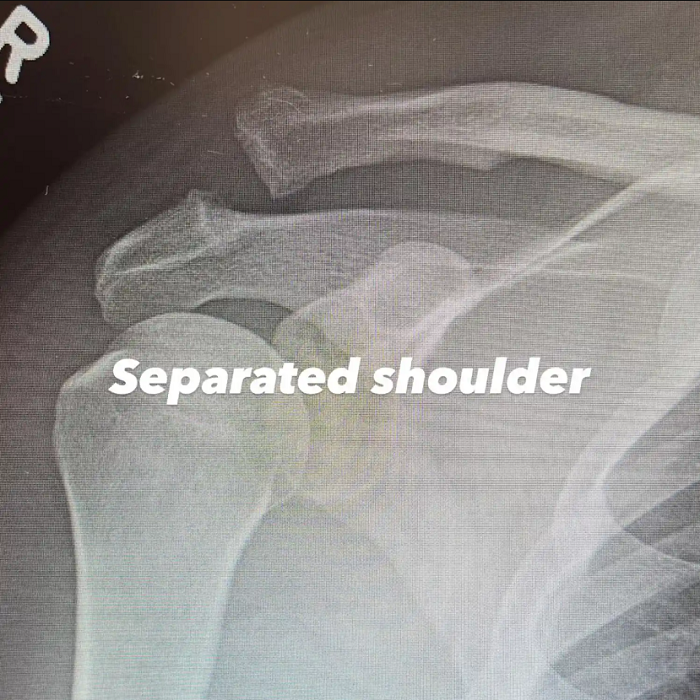

Подоцна, Тејтум преку инстаграм-приказна објасни што точно се случило. Во првата објава сподели рендгенска снимка од горниот дел на раката и рамото, на која јасно се гледа дека две коски се одвоени.

„Раздвоено рамо“, кратко напиша тој.